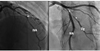

Particularités de l’infarctus du myocarde chez la femme

L’infarctus du myocarde est un problème majeur de santé publique chez les femmes. Les taux d’hospitalisation sont en augmentation, en particulier chez les jeunes femmes. Cette tendance est probablement liée à une prévalence ...